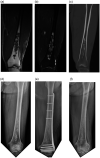

Methods: From April 2000 to December 2016, 37 patients with histologically confirmed low-grade intramedullary chondrosarcoma of the long bones at Kyungpook National University Hospital were enrolled in this retrospective study. All 37 patients underwent intralesional curettage (with or without cryotherapy) followed by bone grafting. Among the 24 patients who underwent cryotherapy, 13 were treated by prophylactic internal fixation (10 in the femur, 1 in the tibia, and 2 in the humerus). Thirteen patients underwent the same treatment without cryotherapy, whereas 12 did not undergo preventive internal fixation.

Results: A single intraoperative fracture was managed by plate fixation. One patient who underwent cryotherapy and internal fixation developed a fracture distal to the operation site 25 days after surgery, and this fracture was repaired with a long plate. None of the 37 patients showed any recurrence or metastasis.

Conclusions: Adequate intralesional curettage (with or without cryosurgery) combined with bone grafting using autogenous and allogeneic bone chips was effective for the treatment of low-grade intramedullary chondrosarcoma. Therefore, prophylactic internal fixation using a plate is recommended in the cryotherapy of definite cortical invasion in weight-bearing bones.